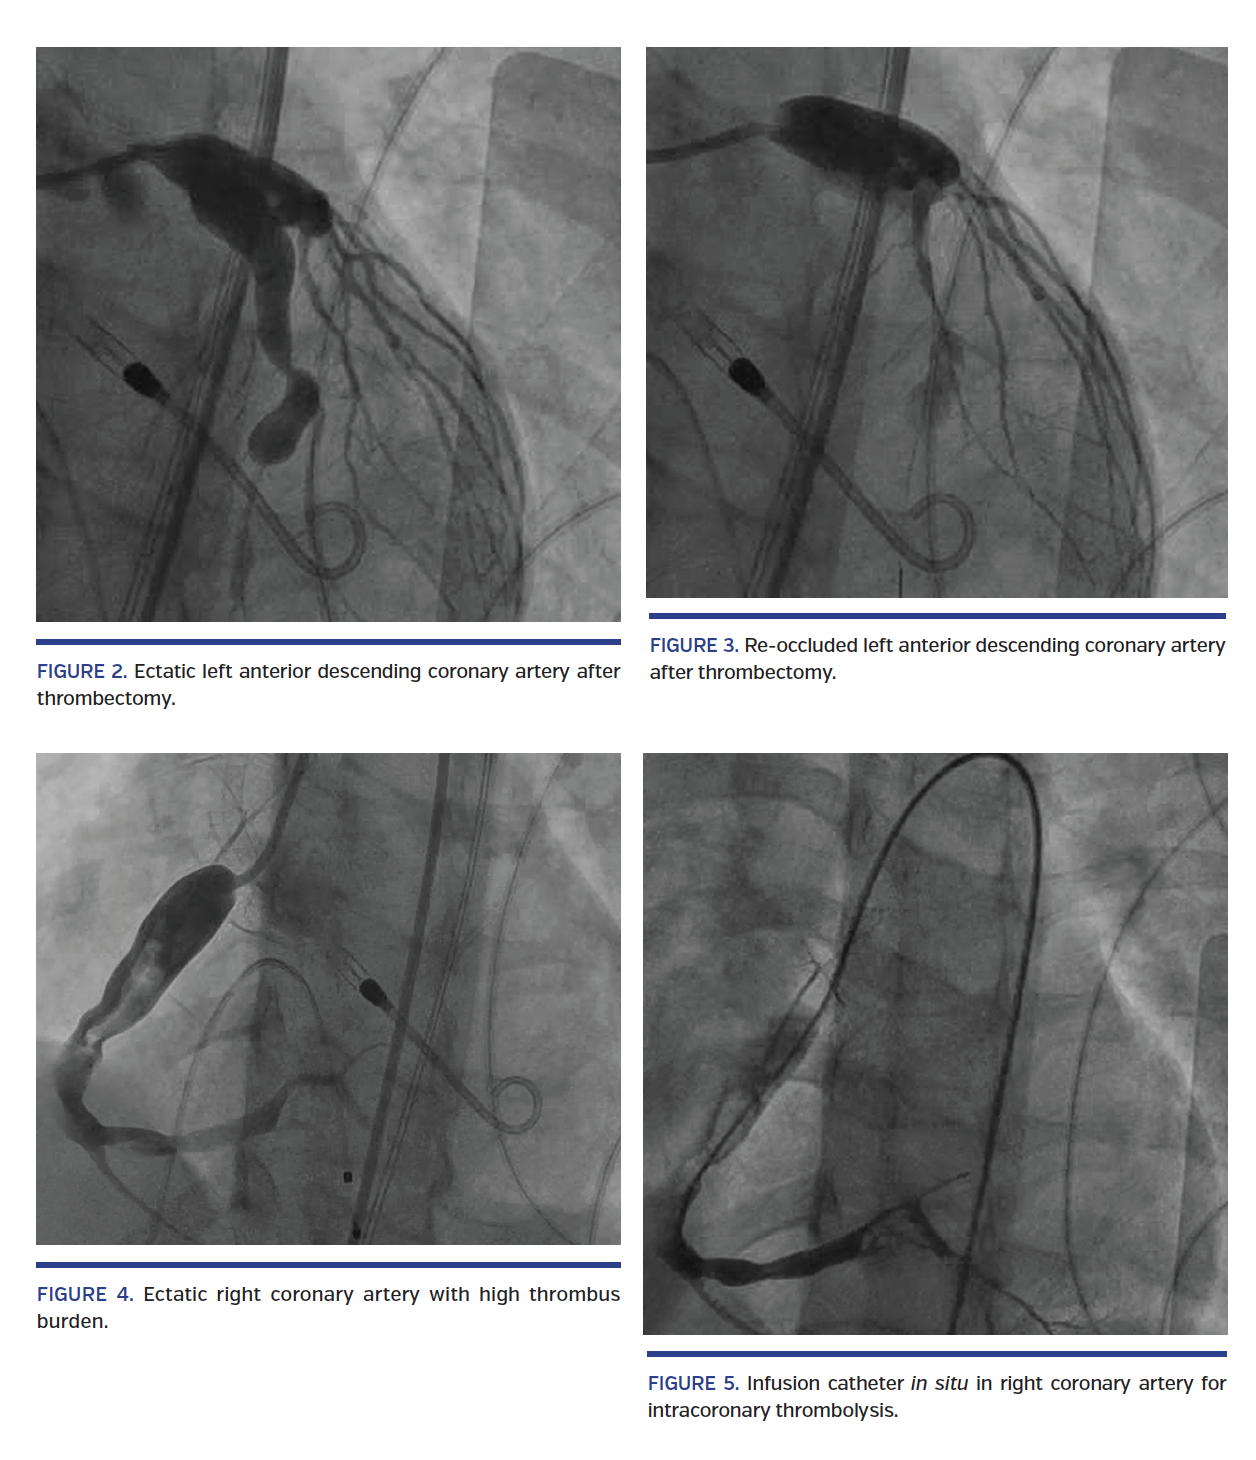

A 15-year-old male with past medical history of Kawasaki disease presented to our emergency room with complaints of severe retrosternal, crushing chest pain at rest associated with nausea and diaphoresis. Physical examination revealed dry mucous membranes. Electrocardiogram showed acute ST-elevation myocardial infarction and laboratory testing showed elevated cardiac enzymes. He was taken to cardiac catheterization laboratory emergently with placement of Impella 2.5 (in view of decreasing left ventricular function) followed by coronary angiography, which showed significantly ectatic left main coronary artery, left anterior descending (LAD) coronary artery, left circumflex (LCX) coronary artery, and right coronary artery (RCA), with associated thrombotic occlusion of the LAD, LCX, and RCA (Figure 1). Intracoronary thrombolysis of the infarct-related artery (RCA) was performed using tissue plasminogen activator 250,000 U/kg 3 times daily for 2 days (Figure 2). Multiple rounds of aspiration thrombectomy followed by balloon angioplasty of the LAD failed to completely restore the flow into the distal LAD secondary to re-occlusion from thrombus formation (Figures 3-5). The patient recovered well with improvement in myocardial pump function, with an ejection fraction of approximately 45%-50% on discharge.